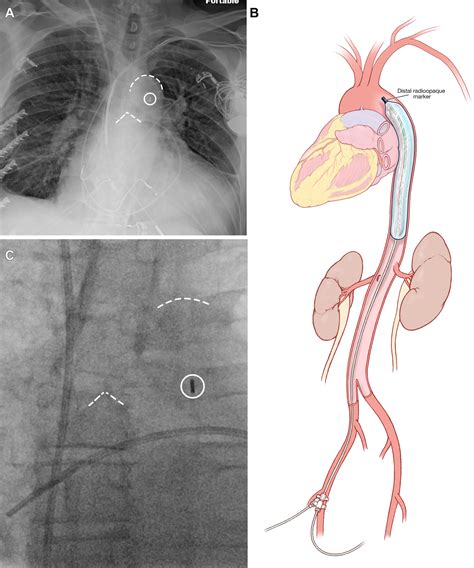

Aortic balloon pump placement, also known as intra-aortic balloon pump (IABP) therapy, is a mechanical circulatory support device used to improve cardiac output and reduce the workload on the heart. The device consists of a catheter with a balloon at the tip, which is inserted into the aorta through a femoral artery. The balloon inflates and deflates in synchrony with the heart's rhythm, providing additional support during diastole and reducing the resistance during systole.

Insertion

The IABP catheter is inserted through the femoral artery and advanced into the aorta. The position of the balloon is confirmed using fluoroscopy or other imaging techniques. The catheter is then secured in place, and the balloon is connected to a console that controls its inflation and deflation.